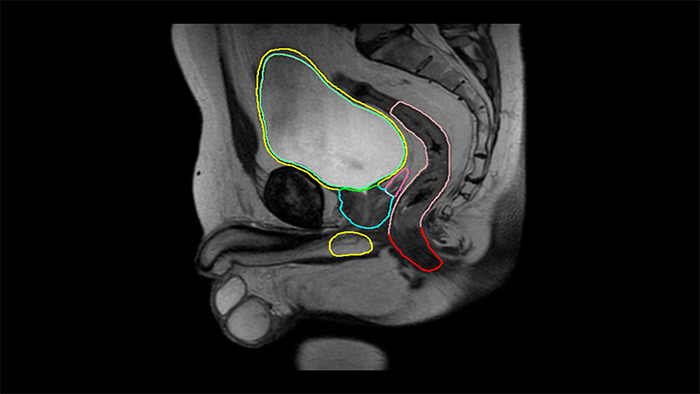

MRCAT Prostate + Auto-Contouring